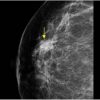

Ung thư vú

Ung thư vú - Ảnh 4

» Thông tin: Nữ giới – 59 tuổi.

» Lâm sàng: Khối tuyến vú.